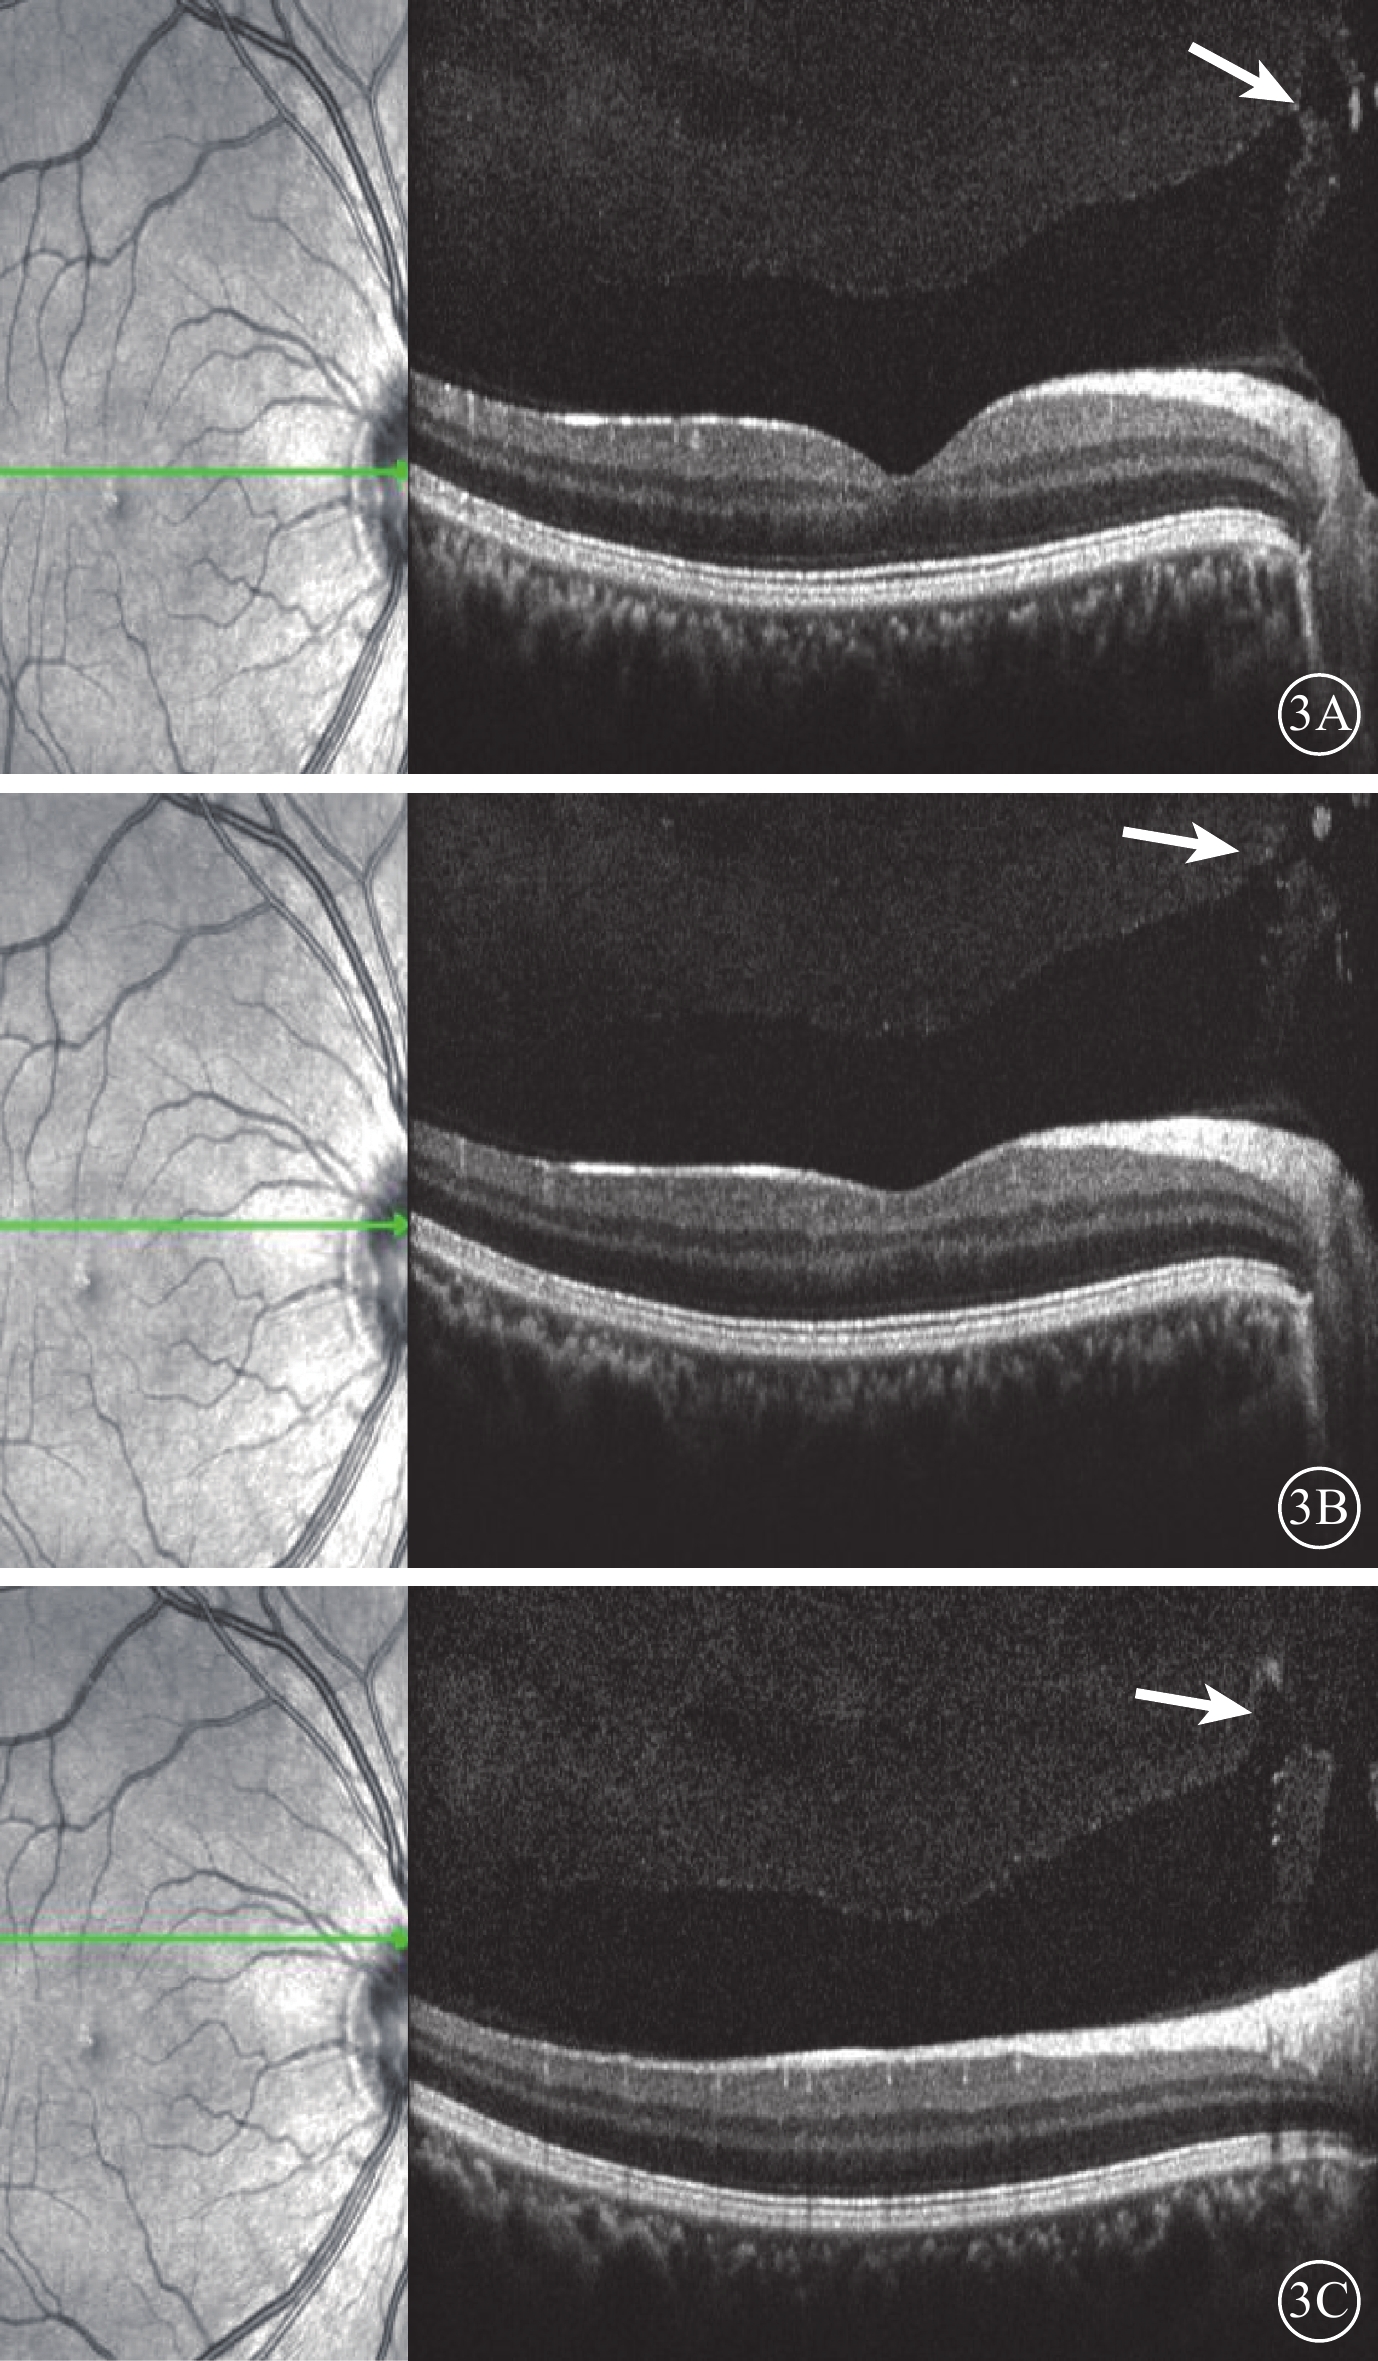

圖3

受檢眼SD-OCT像。左圖為掃描方向和部位;右圖為檢查結果。3A示PPVP與Martegiani區之間出現一小縫隙(白箭);3B示縫隙擴大,可見兩者之間出現連通(白箭);3C示PPVP與Martegiani區之間明顯連接通道(白箭)

圖3

受檢眼SD-OCT像。左圖為掃描方向和部位;右圖為檢查結果。3A示PPVP與Martegiani區之間出現一小縫隙(白箭);3B示縫隙擴大,可見兩者之間出現連通(白箭);3C示PPVP與Martegiani區之間明顯連接通道(白箭)

圖3

受檢眼SD-OCT像。左圖為掃描方向和部位;右圖為檢查結果。3A示PPVP與Martegiani區之間出現一小縫隙(白箭);3B示縫隙擴大,可見兩者之間出現連通(白箭);3C示PPVP與Martegiani區之間明顯連接通道(白箭)

圖3

受檢眼SD-OCT像。左圖為掃描方向和部位;右圖為檢查結果。3A示PPVP與Martegiani區之間出現一小縫隙(白箭);3B示縫隙擴大,可見兩者之間出現連通(白箭);3C示PPVP與Martegiani區之間明顯連接通道(白箭)